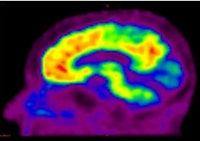

| PiB PET scan shows brain areas containing beta amyloid plaques (yellow and red) in a living person with Alzheimer's. All images courtesy of SNM. |

The two-year Australian Imaging, Biomarkers, and Lifestyle (AIBL) study enrolled 200 patients, which included 34 people with confirmed Alzheimer's and 57 subjects with mild cognitive impairment.

All patients were imaged using PET with carbon-11-labeled Pittsburgh Compound B (C-11 PiB), a PET imaging agent that binds to beta amyloid in neural tissues. The agent can be used to evaluate changes in beta amyloid, which has been linked with the onset of Alzheimer's.

Study results showed that beta amyloid plaque builds slowly over time, and extensive build-up of the protein preceded cognitive impairment and was associated with 13 times the level of risk of progressing to Alzheimer's disease within 20 months. Researchers also found that development of the disease could begin as early as 10 years before signs of dementia.

The authors believe that PET imaging of amyloid build-up in the brain will improve the accuracy of diagnosing Alzheimer's disease and allow physicians to diagnose and foster early treatment.